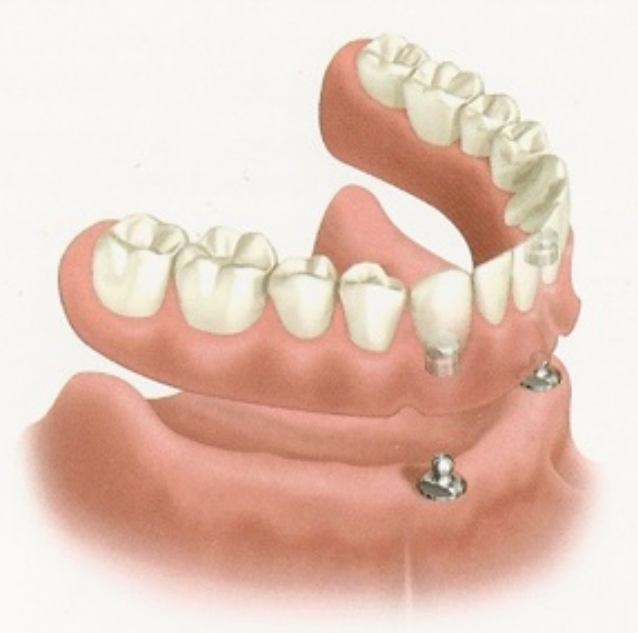

Stabilisation d’un appareil complet mandibulaire à l’aide de Deux implants :

Dans 95% des cas, L’appareil complet mandibulaire (dentier du bas) ne présente ni rétention, ni stabilité: il ne tient tout simplement pas.

Il suffit de poser 2 implants au niveau des canines et d’y placer des boutons pressions pour rétablir le confort d’une prothèse adaptée et rétentive.